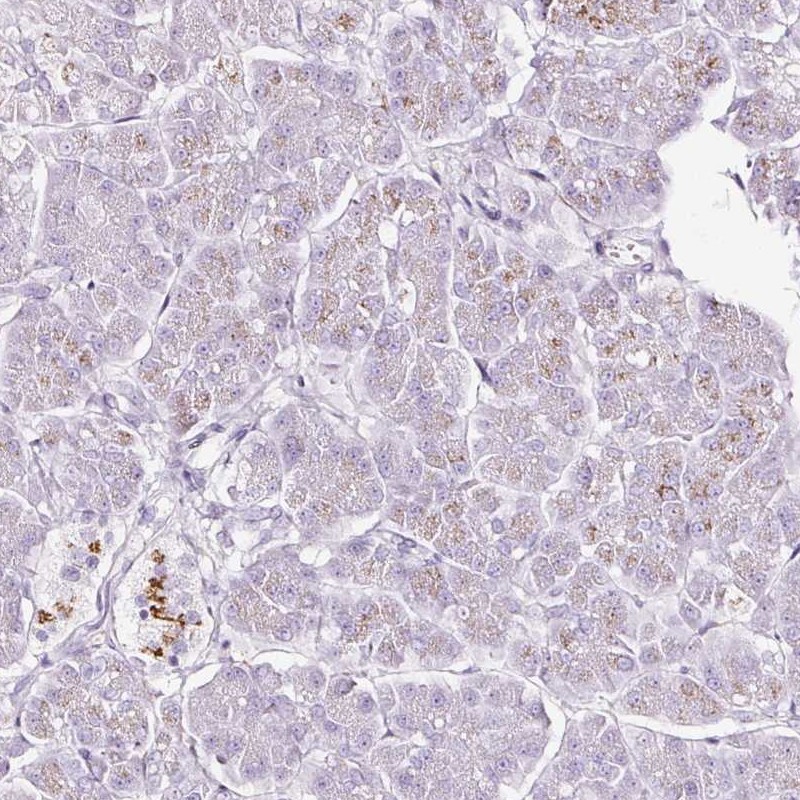

Immunohistochemistry analysis in human small intestine and pancreas tissues using Anti-SDF4 antibody. Corresponding SDF4 RNA-seq data are presented for the same tissues.